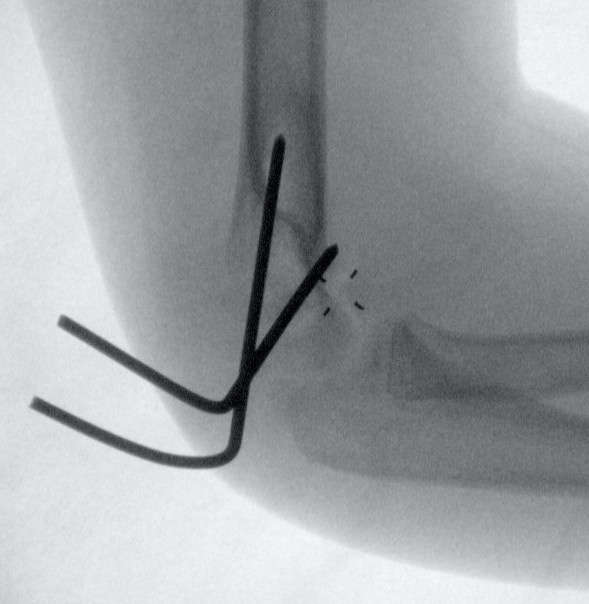

Open reduction and K wires / screw fixation

- one K wire parallel to joint surface across fracture into trochlea

- one K wire at 45 degrees to first engaging medial metaphysis

- bury K wires as need to be in for 6 weeks

Open reduction of displaced lateral condyle in left elbow